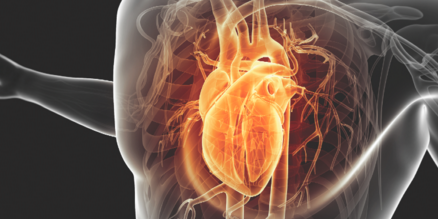

Cardiovascular Issues in the Older Adult

Heart Failure in the Elderly

Sonia Baker, MD; Gautam V. Ramani, MD

It is estimated that more than 5.7 million adults in the United States are living with heart failure (HF).